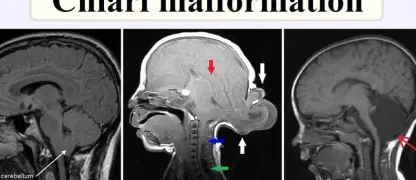

Visualizing concepts related to CTE